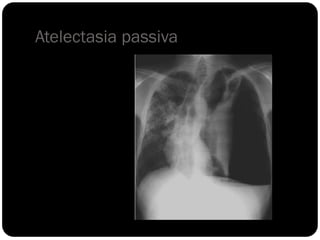

Atelectasia passiva

Sinal da silhueta

Lobo médio: borra o contorno direito do coração.

Língula: borra o contorno esquerdo do coração.

Segmentos basais: borram o contorno do diafragma*** (olhar

imagens anteriores para ver quais).